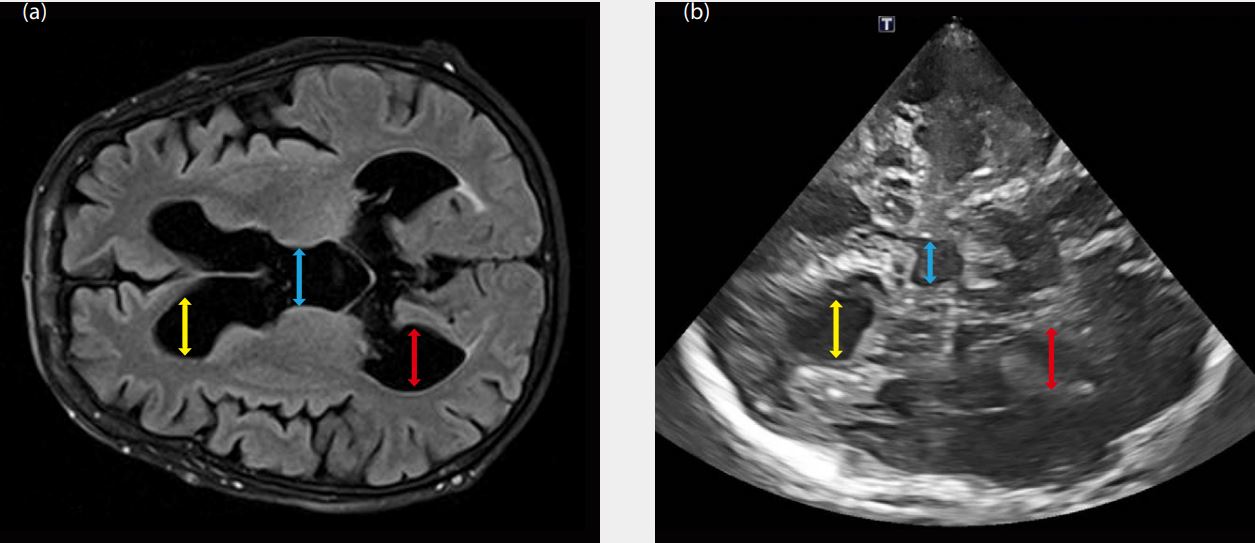

Вивчення проблеми 2

Хворий на ахондроплазію, з явним клінічним погіршенням, утрудненою ходьбою, з явною ретропульсією, нетриманням сечі. Запитання, поставлене клініцисту, може бути таким: «Нормотензивна або гіпертензивна гідроцефалія є?» Ультразвукове дослідження показує:

1. Відсутність набряку сосочка

2. Збільшення ІІІ шлуночка на 20,5 мм

3. Як в аксіальному, так і в корональному скроневому вікні, великі бічні шлуночки, які можна виміряти та контролювати протягом тривалого часу за допомогою ультразвукових досліджень (Мал. 2b)

Малюнок 2 Висновок застосування ультразвукового дослідження в клініці: незалежно від майбутнього обстеження, будь то консервативне чи з тестом Хакіма та подальшим лікуванням, ультразвукове дослідження може контролювати динаміку, не вдаючись до постійних неврологічних досліджень.

Жовта стрілка: збільшений передній бічний шлуночок головного мозку

Синя стрілка: збільшений третій шлуночок

Червона стрілка: збільшений задній бічний шлуночок головного мозку